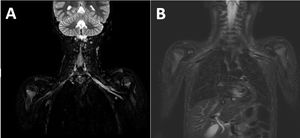

Se realiza RM cerebral y medular, y ante un resultado normal se amplía a RMN de la zona afecta, que revela edema a nivel de los músculos del manguito del rotador e hiperintensidad del plexo braquial (fig. 2).

RMN con hiperintensidad de señal en STIR de los troncos del plexo braquial izquierdo (A y B), sin evidencia de discontinuidad o masas asociadas, observando signos de denervación aguda con leve edema muscular de los músculos supraespinoso e infraespinoso. El cordón medular cervical muestra grosor e intensidad de señal normales, sin evidencia de lesiones ocupantes de espacio en el canal raquídeo. Los cuerpos vertebrales, elementos posteriores y discos intervertebrales muestran morfología, alineación e intensidad de señal normal.